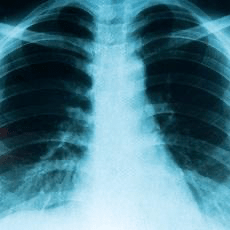

Lung cancer is a disease in which abnormal cells grow in the lungs, usually in the airways, and it is the leading cause of cancer death. There are two main types: small cell lung cancer and non-small cell lung cancer, with the latter being more common. Risk factors include smoking, secondhand smoke, family history of lung cancer, exposure to harmful substances like asbestos or radon, air pollution, and certain medical conditions such as HIV. Symptoms may include a persistent cough, chest pain, coughing up blood, shortness of breath, wheezing, hoarseness, unexplained weight loss, fatigue, loss of appetite, swelling in the face or neck, and trouble swallowing. Lung cancer is diagnosed through a combination of medical history, physical exams, imaging tests like X-rays or CT scans, lab tests, and biopsy. Staging tests are also done to determine if the cancer has spread. Treatment depends on the type and stage of cancer and may include surgery, chemotherapy, radiation, immunotherapy, targeted therapy, laser therapy, photodynamic therapy, cryosurgery, or stent placement. Prevention focuses on quitting or avoiding smoking and reducing exposure to hazardous substances and radon. Early detection and avoiding risk factors are crucial because lung cancer is often diagnosed at an advanced stage.